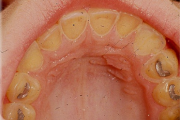

Tetratsükliini liigtarbimise tõttu värvunud hambad

Fluoroos

Fluoroosi

Hammaste defektid

amelogenesis imperfecta

Emaili hüpoplaasiad

Hamba atritsioon